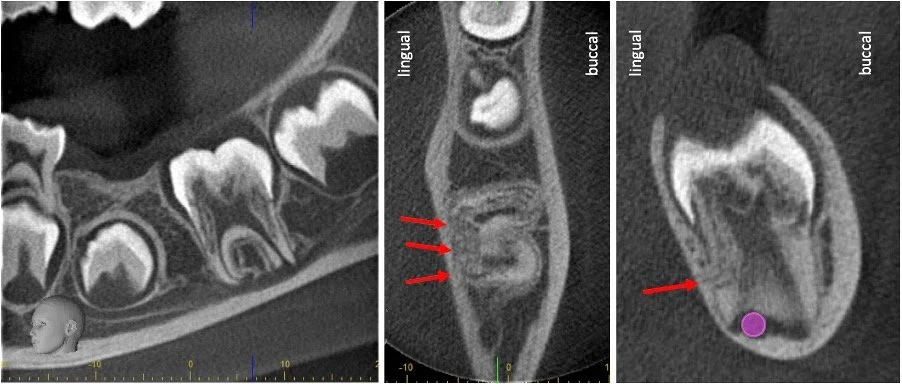

Advanced imaging (CBCT) showing extensive resorption (arrows)

Resorption happens when the body begins to break down part of a tooth or its root structure.